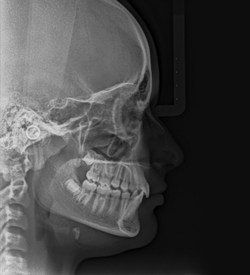

Ortho X - Telerradiografia Lateral

Fornece uma imagem radiográfica do crânio, da face e dos tecidos moles. É indicada para o estudo do crescimento e desenvolvimento das anormalidades crânio-faciais, avaliação progressiva da correção ortodôntica, estudo das relações crânio-faciais, análise funcional e determinação do tipo facial.